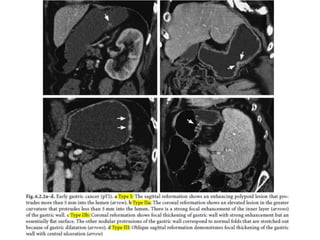

and follow-up examinations with a barium

meal (b) and ultrasound (c)

revealed narrowing of the lumen, typical

irregular folds, and a thickened gastric wall